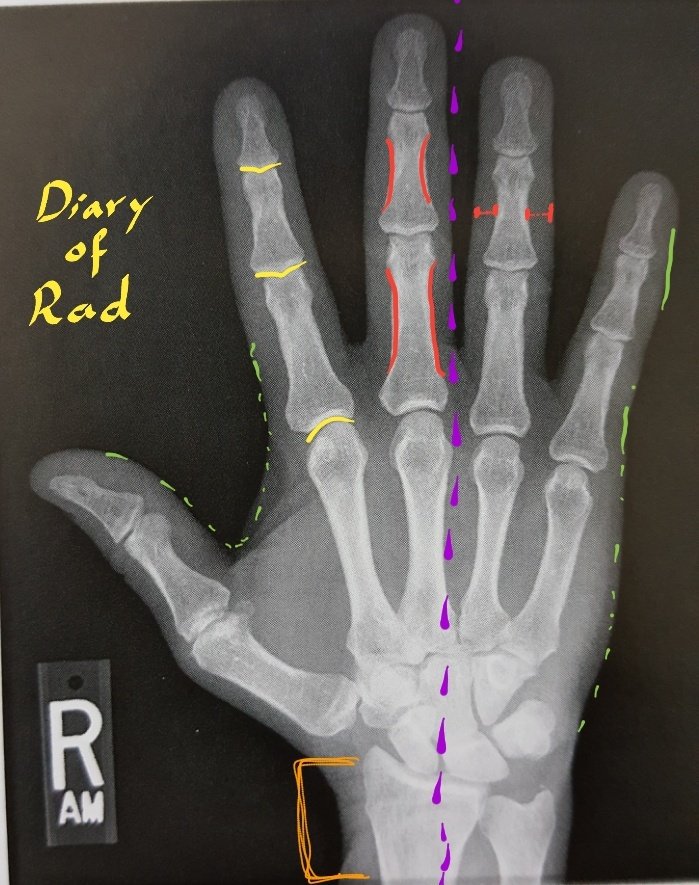

نقد الصورة١:

•يجب أن تظهر عظيمات الرسغ wrist.

•يجب أن يظهر distal forearm.

•مفاصل IP و MCP مفتوحة وواضحة وهذا دليل على أن السنتر في موقعه الصحيح.

•يجب أن يكون الرسغ على امتداد اليد (اليد غير مزاحة لليمين او اليسار بل كلاها على خط واحد).

•تكون الأصابع متباعدة قليلاً.

تابع نقد الصورة٢:

(دليل أن اليد ملتصقة تماماً)

•يجب أن تظهر الأنسجة الرخوة على جانبي عظام الأصابع بشكل متساوي.

•يجب أن تظهر عظام الأصابع منحنية من كلا الجانبين.

•وجود الماركر R or L.

•أن تكون الأنسجة الرخوة ظاهرة بشكل بسيط.

•أن تكون حدود العظام واضحة.

•لايوجد قطع.